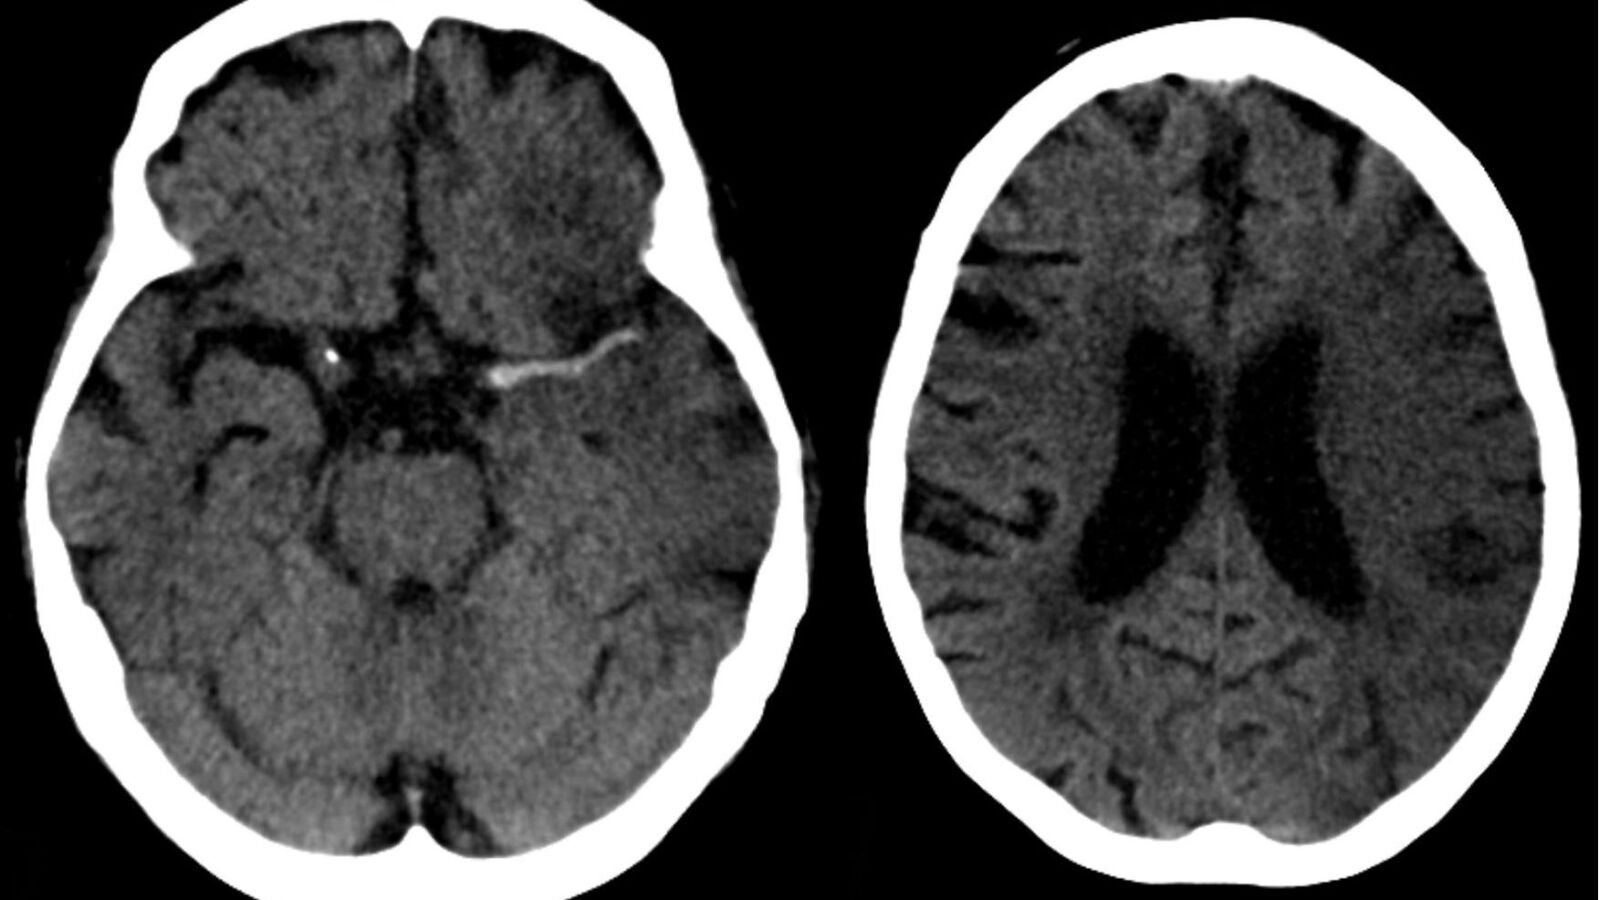

"Cualquier enfermedad que tenga un impacto sobre las arterias -incide Castro- tiene un efecto más rotundo en las arterias de las mujeres", y sus consecuencias varían dependiendo de la zona que ha afectado al vaso infartado, del tiempo que ha estado el cerebro sin recibir sangre y del daño que ha producido.